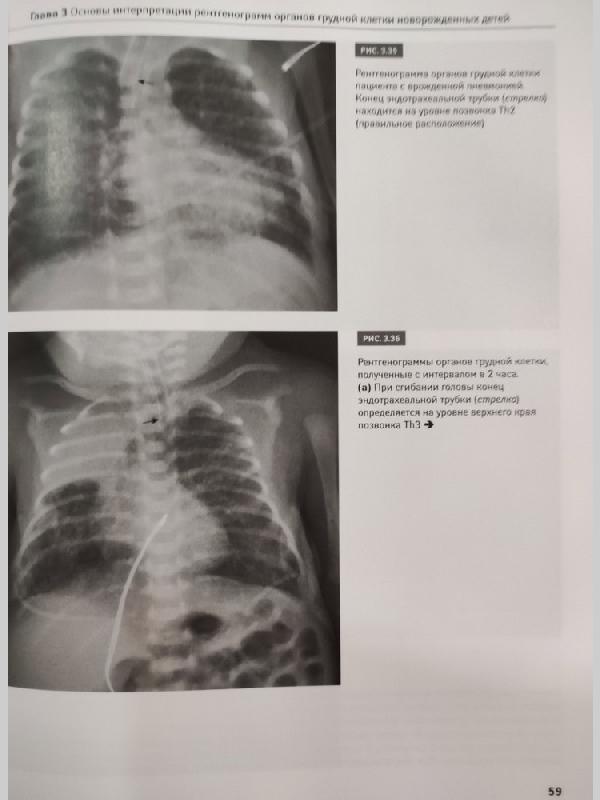

Рентгенодиагностика заболеваний легких у новорожденных детей: монография / М.В. Дегтярева, А.В. Горбунов, А.П. Мазаев, А.В. Ерохина. - М.: Логосфера, 2017. - 200 с. ISBN 978-5-98657-059-4 В монографии изложены основные подходы к рентгенодиагностике заболеваний легких у новорожденных детей, представлены развитие и нормальная анатомия легких, методика рентгенологического исследования, разобраны особенности интерпретации рентгеновских изображений грудной клетки и рентгеносемиотика заболеваний легких у самых маленьких пациентов. Книга содержит более 200 иллюстраций - рисунков и рентгенограмм органов грудной клетки и брюшной полости. Описаны сложные случаи диагностики и дифференциальной диагностики как редких пороков развития, так и часто встречающихся патологических состояний дыхательной системы новорожденных детей. Книга дополнена DVD с файлами рентгенограмм (цифровых и аналоговых), приведенных в книге. Данное издание предназначено для рентгенологов, неонатологов, педиатров, анестезиологов-реаниматологов, врачей скорой помощи, студентов медицинских вузов и других специалистов, работающих в смежных областях.